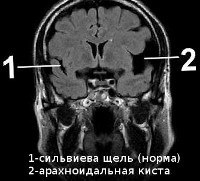

Использование УЗИ позволяет выявить некоторые врожденные кисты еще в период внутриутробного развития, после рождения ребенка и до закрытия его большого родничка диагностика возможна при помощи нейросонографии. В дальнейшем визуализировать кисту можно посредством КТ или МРТ головного мозга. Для дифференцировки кистозного образования от опухоли мозга эти исследования проводят с контрастированием, поскольку в отличие от опухоли, киста не накапливает в себе контрастное вещество. Для лучшей визуализации кистозной полости возможно введение в нее контраста путем пункции кисты. В отличие от МРТ, КТ головного мозга дает возможность судить о вязкости содержимого кисты по плотности ее изображения, что учитывается при планировании хирургического лечения. Основополагающее значение имеет не только установление диагноза, но и непрерывное наблюдение за кистозным образованием для оценки изменения его объема в динамике. При постинсультном генезе кисты дополнительно прибегают к сосудистым обследованиям: дуплексному сканированию, УЗДГ, КТ или МРТ сосудов головного мозга.